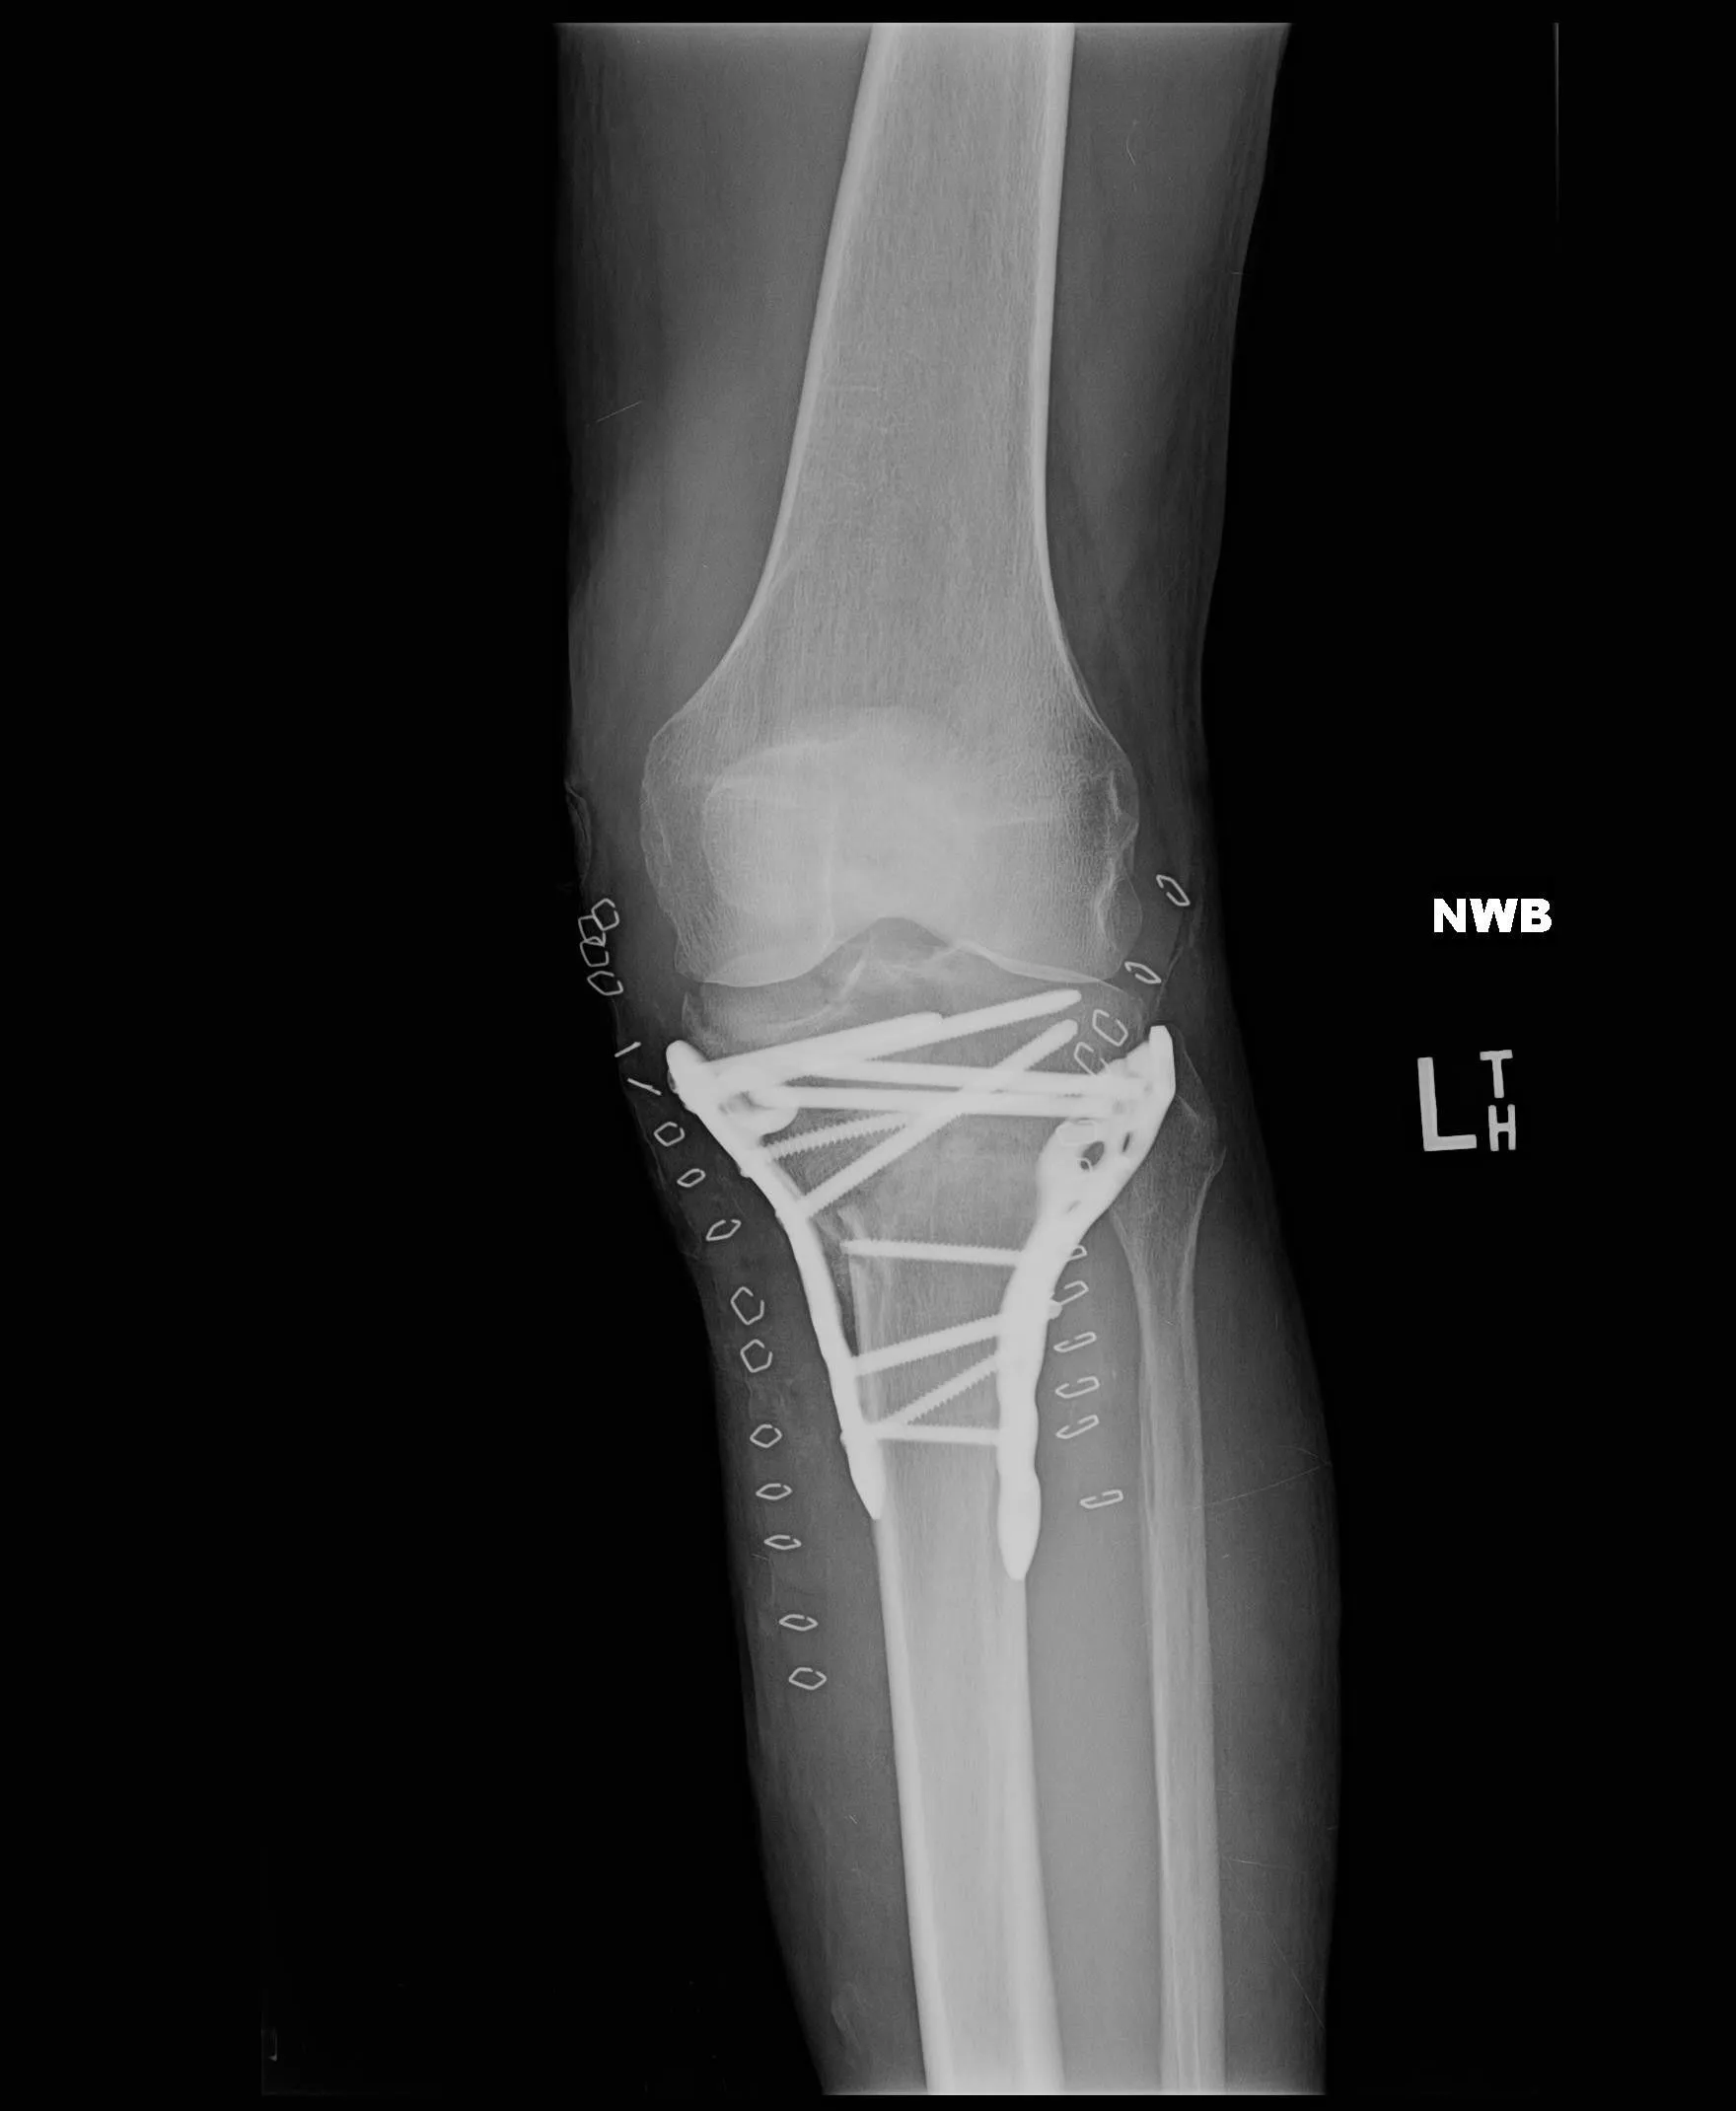

Hot damn! The bionic man lives again!I guess I didn't tell y'all about my knee. In March of '17, I was dismantling a wall of glass block 5 feet high and 20 feet long when it collapsed, trapping me below it. They call the injury a tibia plateau fracture. Basically, I crushed the lower part of my knee where the tibia and fibula join. Had surgery with hardware and bone grafts and was in the hospital for 9 days, bed for 21 days and wheel chair until July. The leg is still not as strong as it should be, but there is no noticeable limp most days until I twist it wrong.View attachment 264988I'm glad you took care of your knees. I had my knee scoped 20 years ago and had forgotten all about it because it worked pretty good. Now, the other knee is bothering me. I think it's the other knee....Had similar experience with compression socks when I was recovering from my knee surgery.How have you been lately, Peach? Mr. Peach still tooling around on his "bike"?